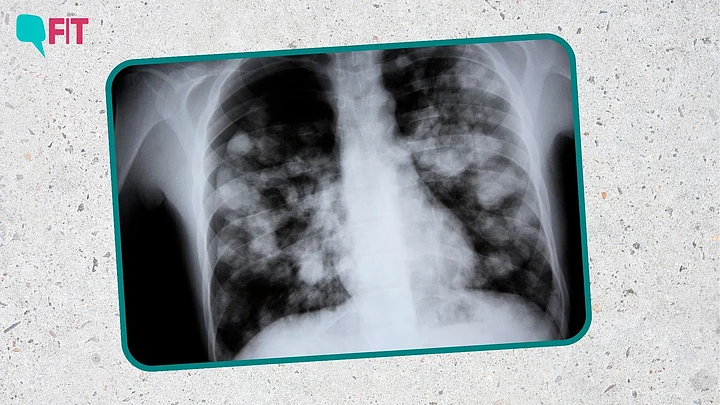

Mycoplasma pneumonia, also called 'white lung syndrome', "is a phenomenon where shadows develop within the lungs, resulting in a whitish appearance," says Dr Guleria.

"It's basically a radiology term," adds Dr Ashok K Rajput.

"Normally the lung contains air which appears black. When this air is replaced by fluid or some secretion, or there is some fibrosis meaning scarring, then it develops white patches. A part of the lung can be white, or the whole lung can be white depending on the severity of the condition."Dr Ashok K Rajput, Senior Consultant, Pulmonology and Sleep Medicine, CK Birla Hospital, Delhi